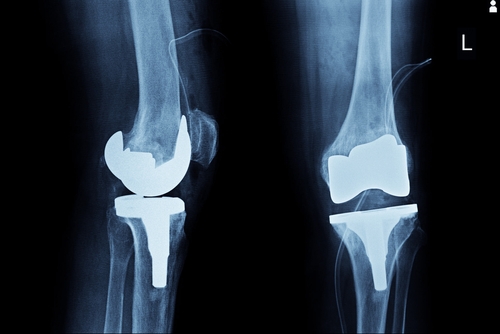

Patients with a defective Exactech knee replacement device who are experiencing the following symptoms should reach out to their physician as soon as possible. Surgeons have already been advised to halt all installations of these knee replacement devices. After meeting with a physician, physicians will conduct a thorough X-ray examination for a more accurate evaluation. Based on the results of the evaluation, physicians may recommend alternative solutions like corrective surgery to resolve the defective issue.